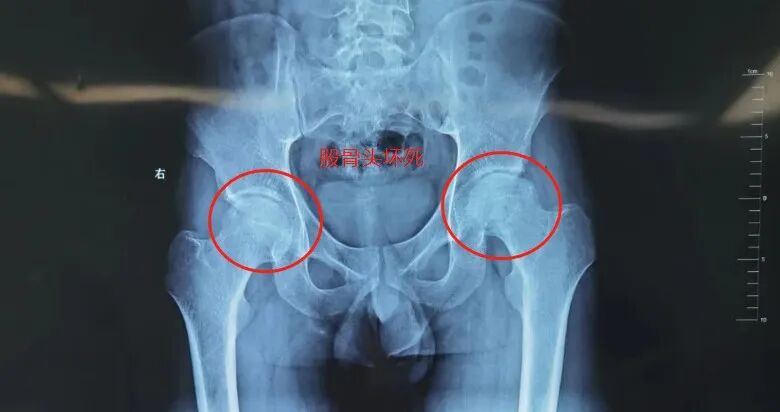

最近,我院骨科接诊了一位患者,50来岁的年龄,却有着15年喝酒的习惯。半年前疼痛突然加剧,别说走路、下蹲,就连躺着都难受。伍见锋主任详细询问病史并结合影像学检查,诊断该患者左侧股骨头缺血性坏死晚期,已经塌陷变形。保髋治疗已经没有意义,需要施行人工髋关节置换术。

知道此结果后,患者崩溃痛苦地表示:“为什么得这个病?”其实,他的股骨头坏死,病因正是最典型的长期酗酒。由于长期过量饮酒导致的股骨头血液中断或受损,引起骨细胞与骨髓成分死亡,导致髋关节疼痛,股骨头塌陷变形,使髋关节功能逐渐丧失。